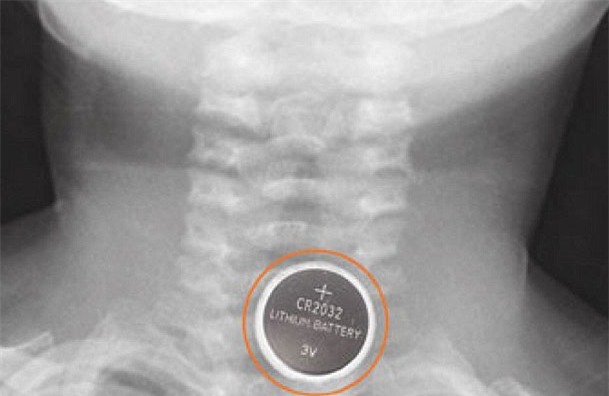

Nhà chức trách Anh đã buộc phải đưa ra các cảnh báo mới trên về sự nguy hiểm của pin cúc áo, sau khi có 2 trường hợp trẻ em thiệt mạng vì mắc nghẹn chúng trong cổ họng. Loại pin trông có vẻ vô hại còn được phát hiện gây vô số thương tích nghiêm trọng khi kẹt cứng trong cổ họng của các nạn nhân và giải phóng ra một axit gây bỏng nặng.

Các chuyên gia cho biết, những loại pin cúc áo mới, nhỏ bé hơn thậm chí còn nguy hiểm hơn do rất dễ lọt sâu vào cổ họng người. Khi viên pin bị mắc kẹt, nó sản sinh một dòng điện khi tiếp xúc với thành cổ họng, tạo sự tích tụ xút ăn da gây bỏng nặng. Ngay cả sau khi viên pin đã được loại bỏ, nó vẫn có thể tiếp tục gây bỏng và tổn thương nghiêm trọng.

Tiến sĩ Parkins nhấn mạnh: "Điều quan trọng là cha mẹ cần ý thức được sự nguy hại mà pin cúc áo có thể gây ra. Trẻ dưới 6 tuổi có rủi ro bị tổn hại vì loại pin này nhất, nhưng thương tích nghiêm trọng có thể xảy ra với bất kỳ nhóm tuổi nào. Các trường hợp nặng nhất thường gắn liền với các loại pin Lithium cúc áo mới, lớn hơn 20mm, có thể gây tổn thương chỉ trong vòng 2 tiếng đồng hồ sau khi mắc kẹt trong cổ họng.